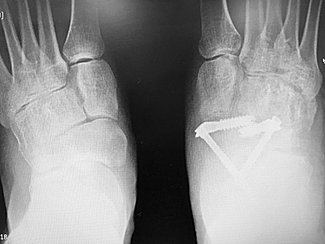

If you later develop problems with any of the other structures in your foot or ankle in the future they may require further surgery. Flatfoot with talonavicular arthritis before and after talonavicular fusion with the subtalar implant. I am 72 years old but i have good bones.

Fusion is the gold standard procedure to treat severe pain and deformity associated with advanced arthritis in the foot and ankle. Talonavicular fusions are done for two main reasons: A talonavicular fusion fuses the talus and the navicular bones.

Surgery to fuse the talonavicular joint will address only one of these joints. What does fusing the talonavicular joint mean for foot movement? By fusion of a major joint in the middle of the foot, called the talonavicular joint.